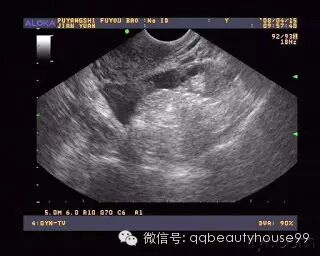

3、B超:患侧卵巢增大或包块形成,盆腹腔积液。